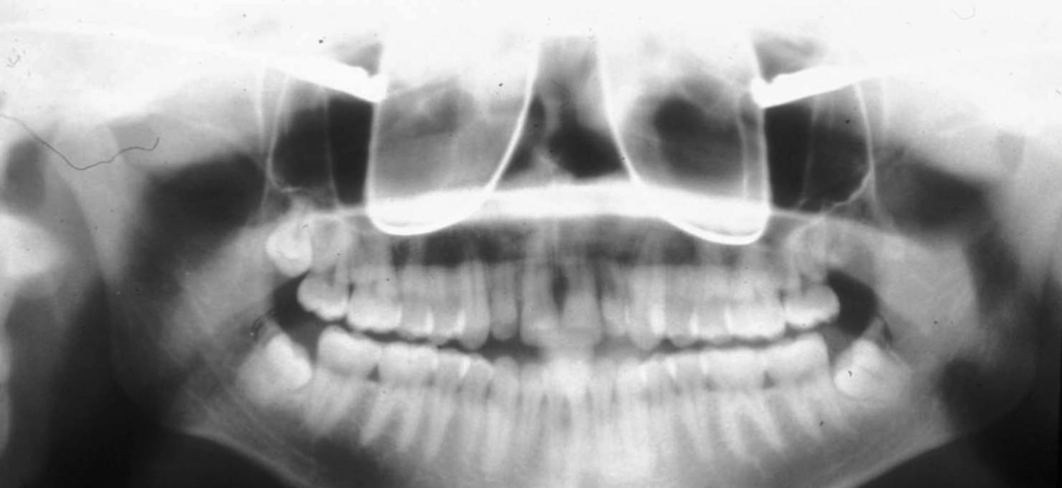

What are some errors that can be seen on this radiograph? What is the cause?

1. flat occlusal plane or reverse curvature 2. roots of maxillary anterior teeth are blurred 3. rami/condyles tipped laterally 4. condyles close to or cut off side of image 5. hard palate superimposed on maxillary apices Cause: chin up